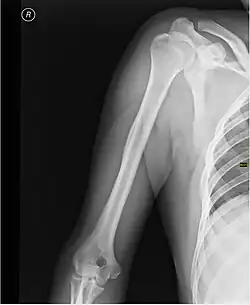

Каркасом плеча служит плечевая кость.

При травмах плеча возможно повреждение нервов и сосудов, а также переломы плечевой кости, наиболее частой локализацией которых является шейка плечевой кости[1].